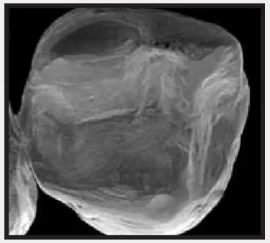

復(fù)合樹脂在即刻充填后,觀察其在電子顯微鏡下的掃描圖像,本次研究選擇了9種具有代表性的復(fù)合樹脂材料。

1.png